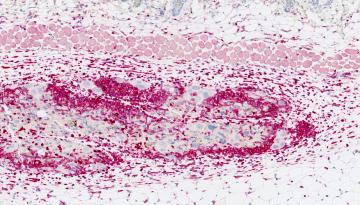

2022: Enguany, s'han realitzat avenços notables en la investigació sobre el càncer i la metàstasi i els transtorns relacionats amb el metabolisme i l’envelliment. També s’ha progressat en la comprensió fonamental dels mecanismes subjacents a la salut i a la malaltia. La nostra recerca ha tingut un gran impacte, tant en la comunitat científica com en la societat en general.